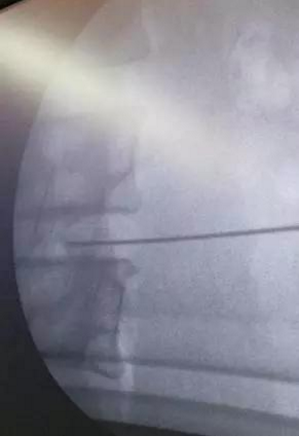

针对他的病情,王林华主任制定了微创臭氧联合射频消融术方案。手术是在局麻下进行的,在C型臂机引导下精确定位,通过特定的穿刺导针精确输出超高频电波,使局部组织产生局部高温,起到热凝固或使椎间盘髓核消融固缩作用,从而治疗椎间盘突出症。

(针孔准确刺入,进行治疗)

(穿刺导针输出超高频电波)